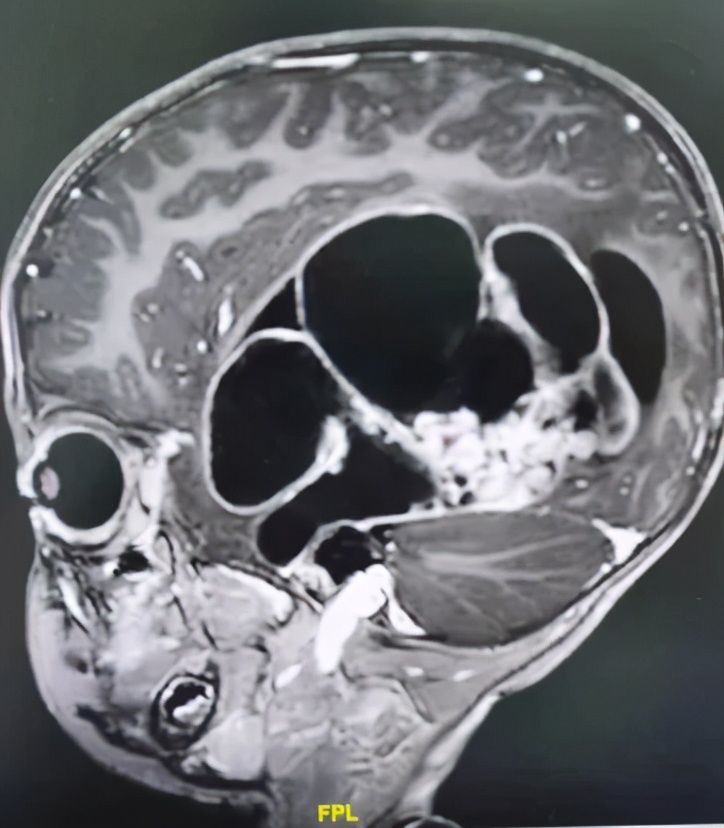

五一假期刚结束,付先生夫妻怀抱2岁儿子小烨,怀着最后一丝希望匆忙赶到中肿找到王翦主任医师。通过仔细检查,王翦主任医师初步判定小烨颅内巨大肿物位于左侧颞顶枕叶,性质考虑恶性室管膜瘤可能性大。肿物巨大,直径达11cm,除了破坏左侧颞顶枕叶脑组织,累及脑室系统并将呼吸和心跳中枢脑干往右侧推移2cm,颅高压明显,随时都可能有生命危险。

脑和心脏一样都是单器官,不同部位的脑有不同的功能,精准调控着人类大部分的身心活动。2岁的小烨头颅最长径15cm,而脑内的肿瘤侵犯了左侧颞顶枕叶等,直径达恐怖的11cm,几乎波及整个左侧大脑!手术是最关键的救命手段,但脑内肿瘤异常巨大,备受病痛折磨的小烨体重仅有11公斤,机体代偿功能非常不完善,手术面临出血性休克、失语和肢体肌力下降等巨大风险。但看着付先生夫妻渴望而无助的眼神,王翦主任医师又一次下决心收治了这一辗转两广多家医院的疑难病例。

术前MR:头的最大直径15cm,而肿瘤直径达到了惊人的11cm